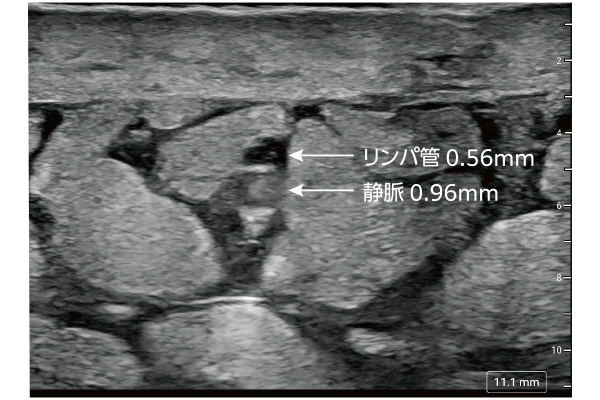

リンパ管の位置や状態を詳細に把握できることにより、外科的治療の精度向上を支援します。